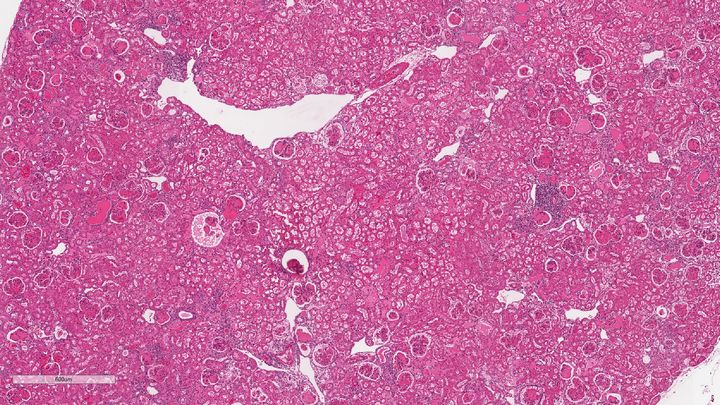

Gallery